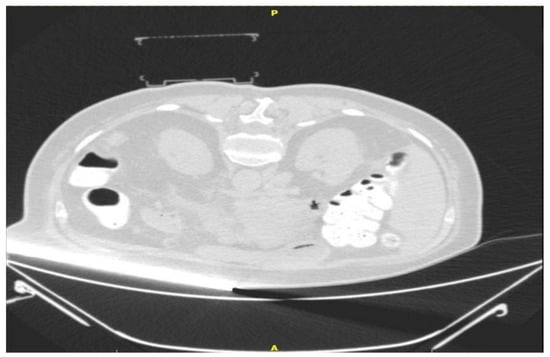

Figure 2. Initial CT scan with target and the cube mounted on the skin.

The “CNS” (Medical Templates AG, Egg, Zurich, Switzerland) was described recently in detail in an ex vivo study [3]. In short, the PC is a disposable cube-shaped apparatus consisting of an upper- and a lower-grid template, with fields marked both with letters and numbers (e.g., field B2). This cubic-shape apparatus will collapse during a puncture if the needle is too short, or if the needle path needs to be adjusted. The pre-mounted adhesive on every foot of the cube allows for fixation on the skin of the patient. The PC consists of polypropylene, which is hyperdense on CT planning scans (approx. −200 Hounsfield units) (Figure 2).